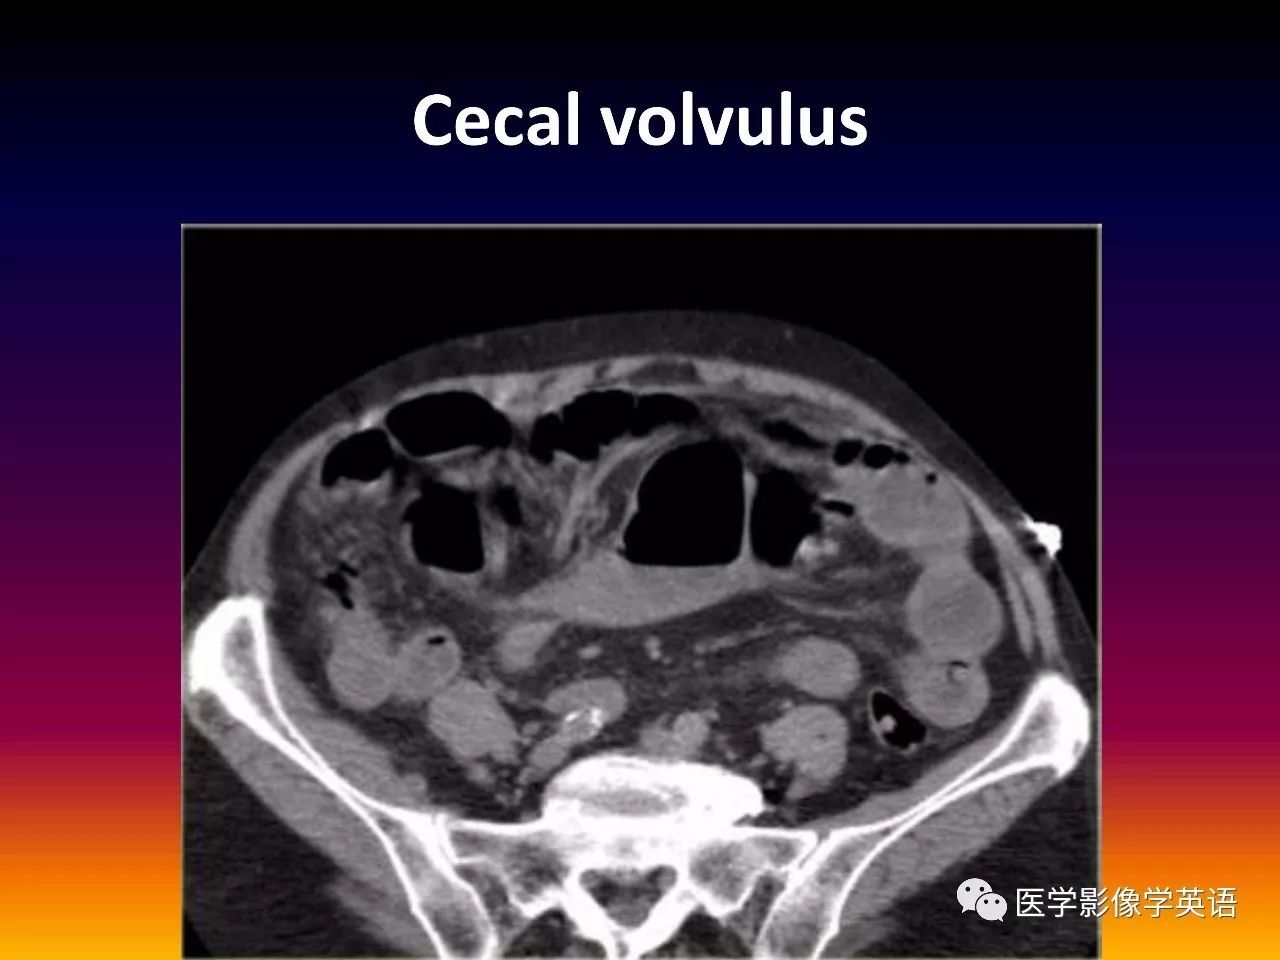

93. Cecal volvulus

94. Cecal volvulus

95. Cecal volvulus

96. Cecal volvulus

97. Cecal volvulus

98. Cecal volvulus

99. Cecal volvulus

100. Cecal volvulus